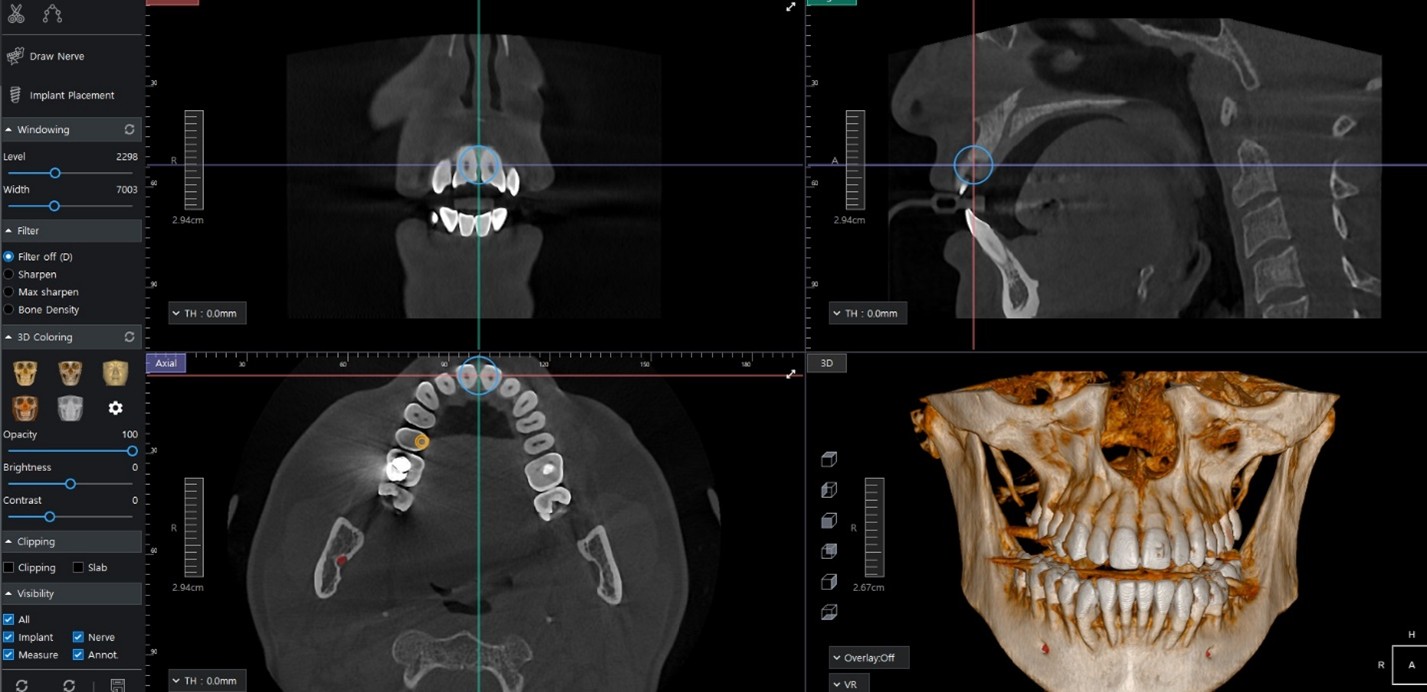

CBCT technology allows our dentists to view the teeth, jawbone, nerves, and surrounding structures in remarkable detail—helping us diagnose dental concerns accurately and create customized treatment plans designed for long-term success.

CBCT imaging provides a complete three-dimensional view of your oral anatomy, offering important advantages over traditional dental X-rays.

Our CBCT machine allows our dental team to plan treatments with exceptional accuracy, improving safety and predictability for procedures such as:

By mapping nerves, bone density, and surrounding structures in advance, we can minimize risks and deliver more comfortable, efficient care.

We believe informed patients feel more confident—and CBCT imaging helps us explain your condition and treatment options clearly, using visual, easy-to-understand images.